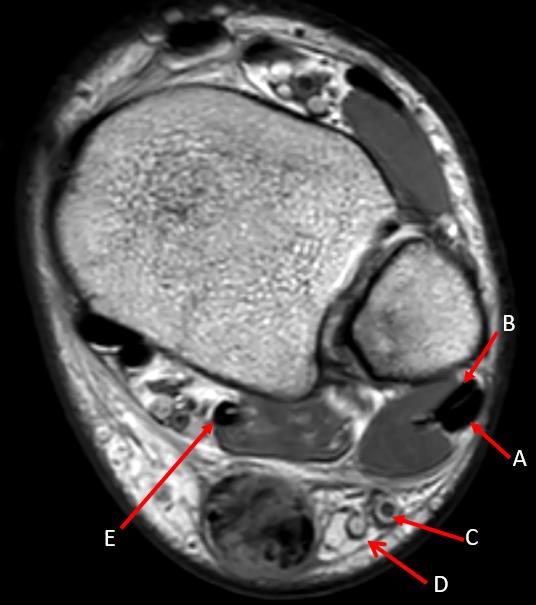

summary Achilles Tendon Ruptures are common tendon injuries that occur due to sudden dorsiflexion of a plantarflexed foot, most commonly associated with sporting events. Diagnosis can be made clinically with weakness of plantarflexion with a positive Thompson's test. MRI studies may be indicated for surgical management of chronic injuries. Treatment may be nonoperative or operative depending on patient age, patient activity demands and chronicity of injury. Epidemiology Incidence 18:100,000 per year may be missed in up to 25% Demographics more common in men most common in ages 30-40 Risk factors episodic athletes, "weekend warrior" flouroquinolone antibiotics steroid injections Etiology Mechanism usually traumatic injury during a sporting event may occur with sudden forced plantar flexion violent dorsiflexion in a plantar flexed foot Pathoanatomy rupture usually occurs 4-6 cm above the calcaneal insertion in hypovascular region Anatomy Achilles tendon largest tendon in body formed by the confluence of soleus muscle tendon medial and lateral gastrocnemius tendons blood supply from posterior tibial artery Presentation History patient usually reports a "pop" Symptoms weakness and difficulty walking pain in heel Physical exam inspection increased resting ankle dorsiflexion in prone position with knees bent calf atrophy may be apparent in chronic cases palpation palpable gap motion weakness to ankle plantar flexion increased passive dorsiflexion provocative test Thompson test lack of plantar flexion when calf is squeezed Imaging Radiographs indications used to rule out other pathology Ultrasound indications may be useful to determine complete vs. partial ruptures MRI indications equivocal physical exam findings chronic ruptures findings will show acute rupture with retracted tendon edges Treatment Nonoperative functional bracing/casting in resting equinus indications acute injuries with surgeon or patient preference for non-operative management sedentary patient medically frail patients outcomes equivalent plantar flexion strength compared to operative management new studies show equivalent rates of re-rupture if functional rehabilitation used versus operative repair fewer complications compared to operative treatment Operative open end-to-end achilles tendon repair indications acute ruptures (approximately <6 weeks) outcomes decreased rate of re-rupture compared to non-operative management new Level 1 evidence has suggested no difference in re-rupture rates with functional rehab protocol no significant difference in plantar flexion strength with functional rehab protocol decreased risk of re-rupture after surgical repair when early ROM protocol used percutaneous Achilles tendon repair indications concerns over cosmesis of traditional scar outcomes higher risk of sural nerve damage lesser risk of wound complications/infection compared with open repair more rapid return to work, with equivalent 1-year function compared with open repair. reconstruction with VY advancement indications chronic ruptures with defect < 3cm flexor hallucis longus transfer +/- VY advancement of gastrocnemius indications chronic ruptures with defect > 3cm requires a functioning tibial nerve Techniques Functional bracing/casting in resting equinus technique cast/brace in 20 degrees of plantar flexion early functional rehab for those treated without a cast End-to-end achilles tendon repair approach make incision just medial to achilles tendon to avoid sural nerve technique incise paratenon expose tendon edges repair with heavy non-absorbable suture postoperative care immobilize in 20° of plantar flexion to decrease tension on skin and protect tendon repair for 4-6 weeks Percutaneous achilles tendon repair technique Reconstruction with VY advancement technique make V cut with apex at musculotendinous junction with limbs divergent to exit the tendon V is incised through only the superficial tendinous portion leaving the muscle fibers intact Flexor hallucis longus transfer ± VY advancement of gastrocnemius technique excise degenerative tendon edges release FHL tendon at the Knot of Henry and transfer through the calcaneus residual hallux plantarflexion weakness Complications Re-rupture incidence higher with non-operative management (~10-40% vs 2%) new Level 1 evidence has shown no difference in re-rupture rates treatment surgical repair Wound healing complications incidence 5-10% risk factors smoking (most common) female gender steroid use open technique (versus percutaneous) treatment deep infection debridement of necrotic/infected Achilles tendon culture-specific antibiotics for 6 weeks Sural nerve injury incidence higher when percutaneous approach is used